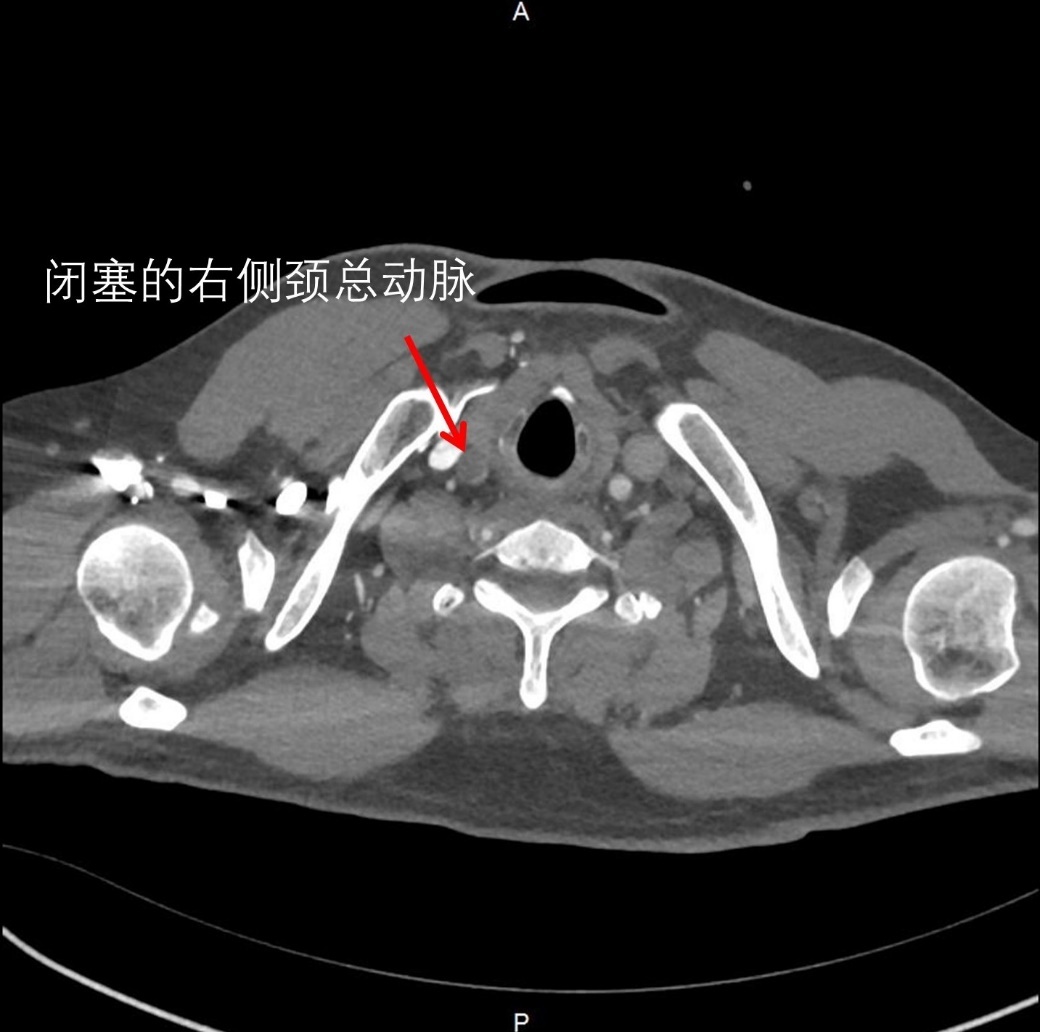

11月初的深夜,一位60岁左右的男性患者因突发胸背部剧烈疼痛被送往新华医院奉贤院区急诊。主动脉CTA检查结果显示,患者确诊为A型主动脉夹层,夹层范围从心脏根部延伸至胸、腹部及下肢,更危急的是,夹层已累及供应右侧大脑的右颈总动脉,导致血管完全闭塞,右侧大脑血供中断。

图2: 供应右侧大脑血供的大动脉被夹层挤压闭塞

入院时,患者左侧肢体已无法活动,意识逐渐模糊,濒临昏迷,生命岌岌可危。“时间就是大脑,时间就是生命!”若长途转运,大脑每缺血一分钟,恢复希望便减少一分。面对紧急状况,心胸外科主任当机立断,决定在奉贤院区实施手术。